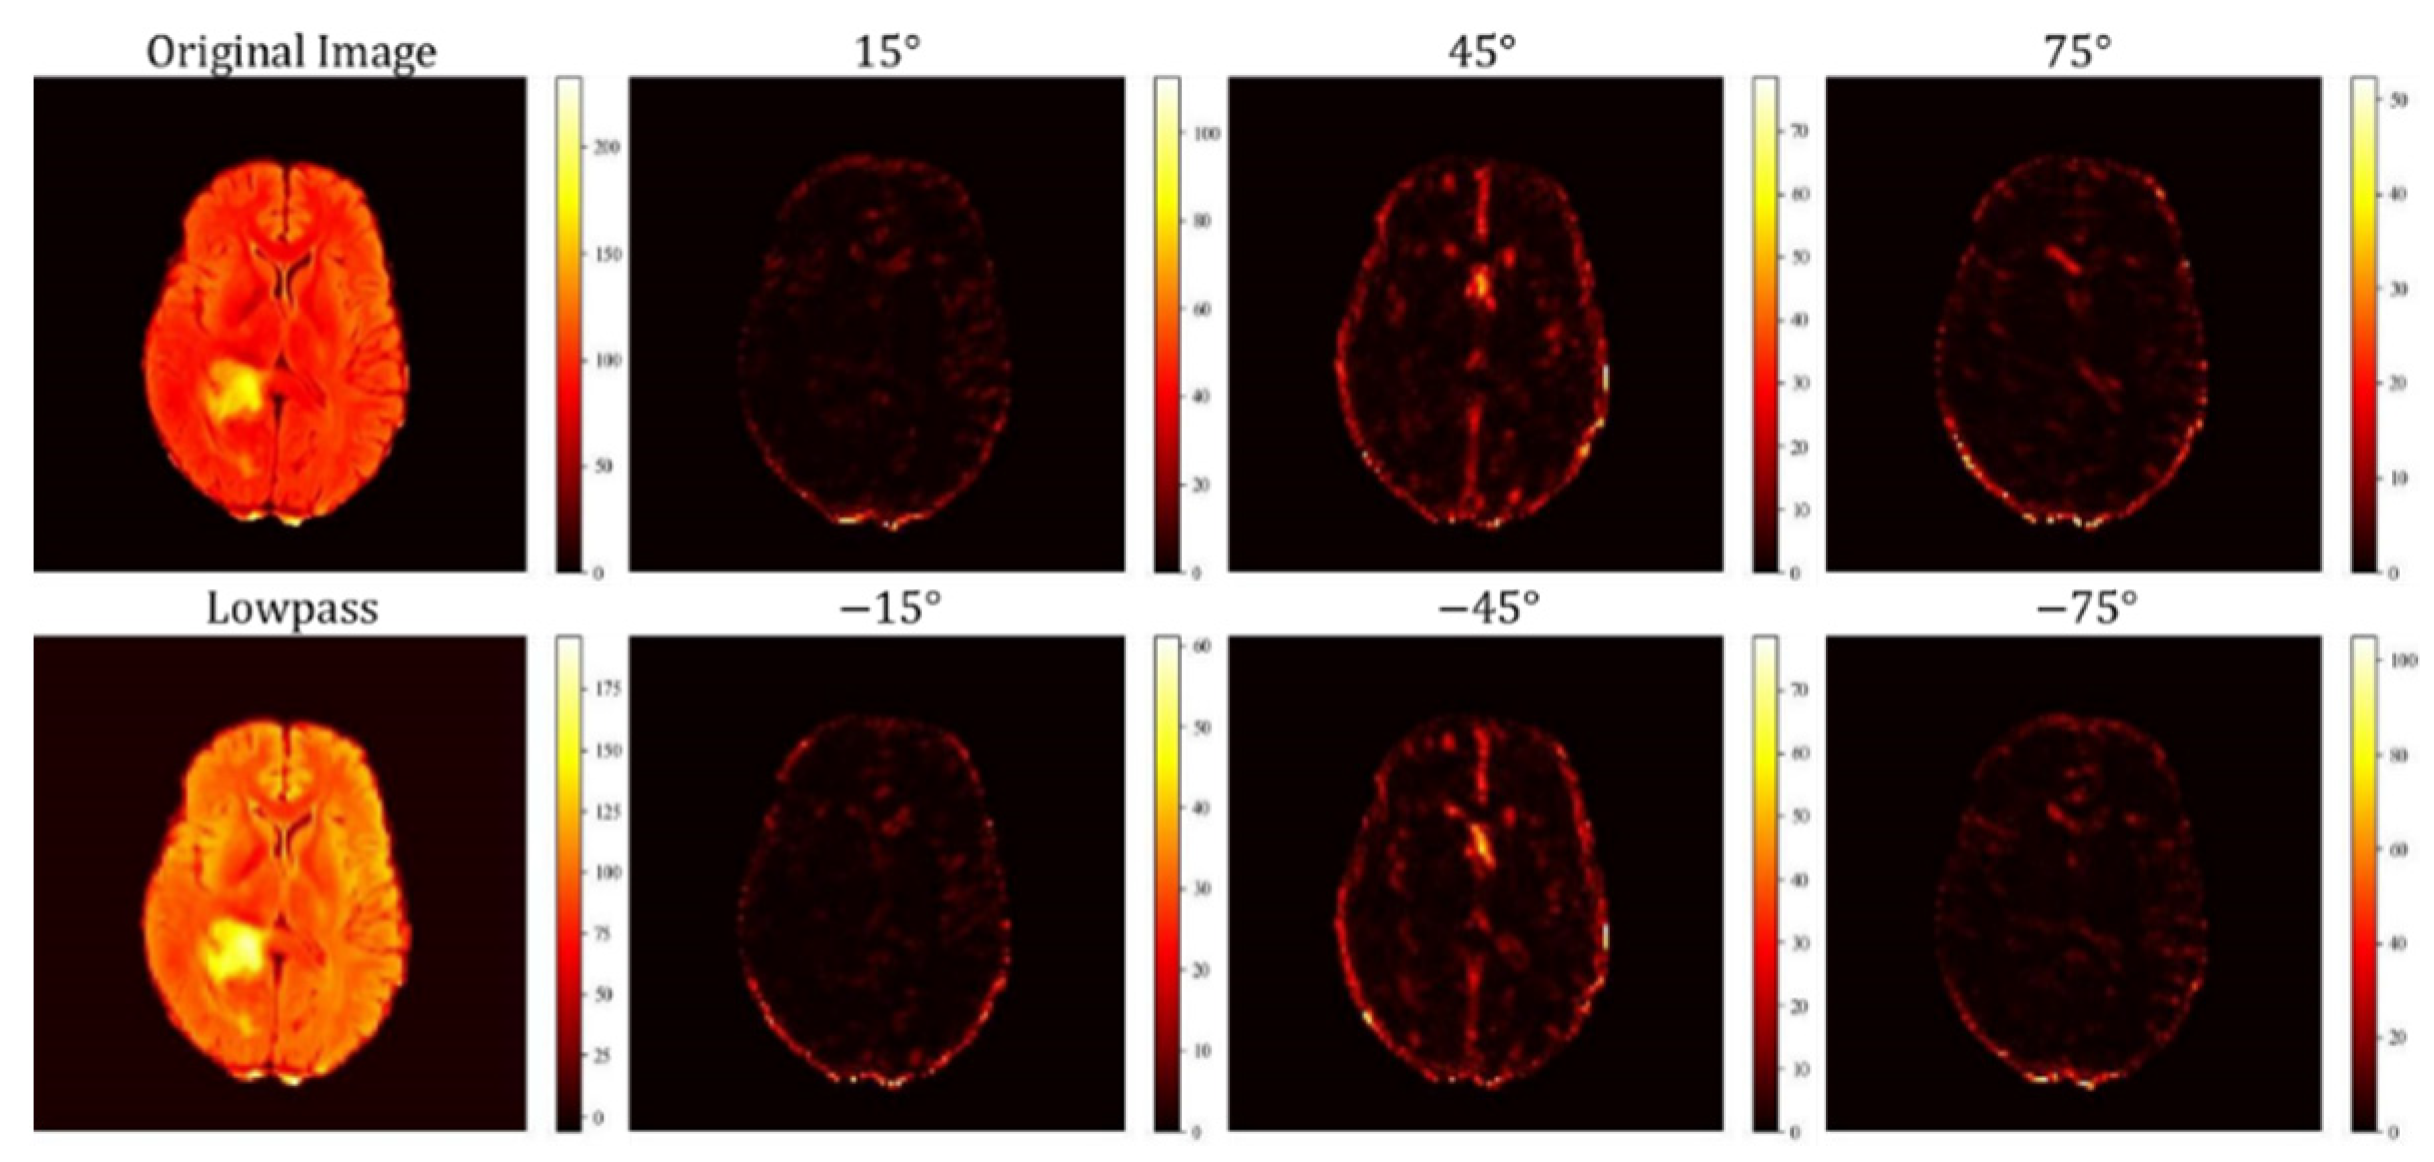

3.2. DTCWT-Scat Module